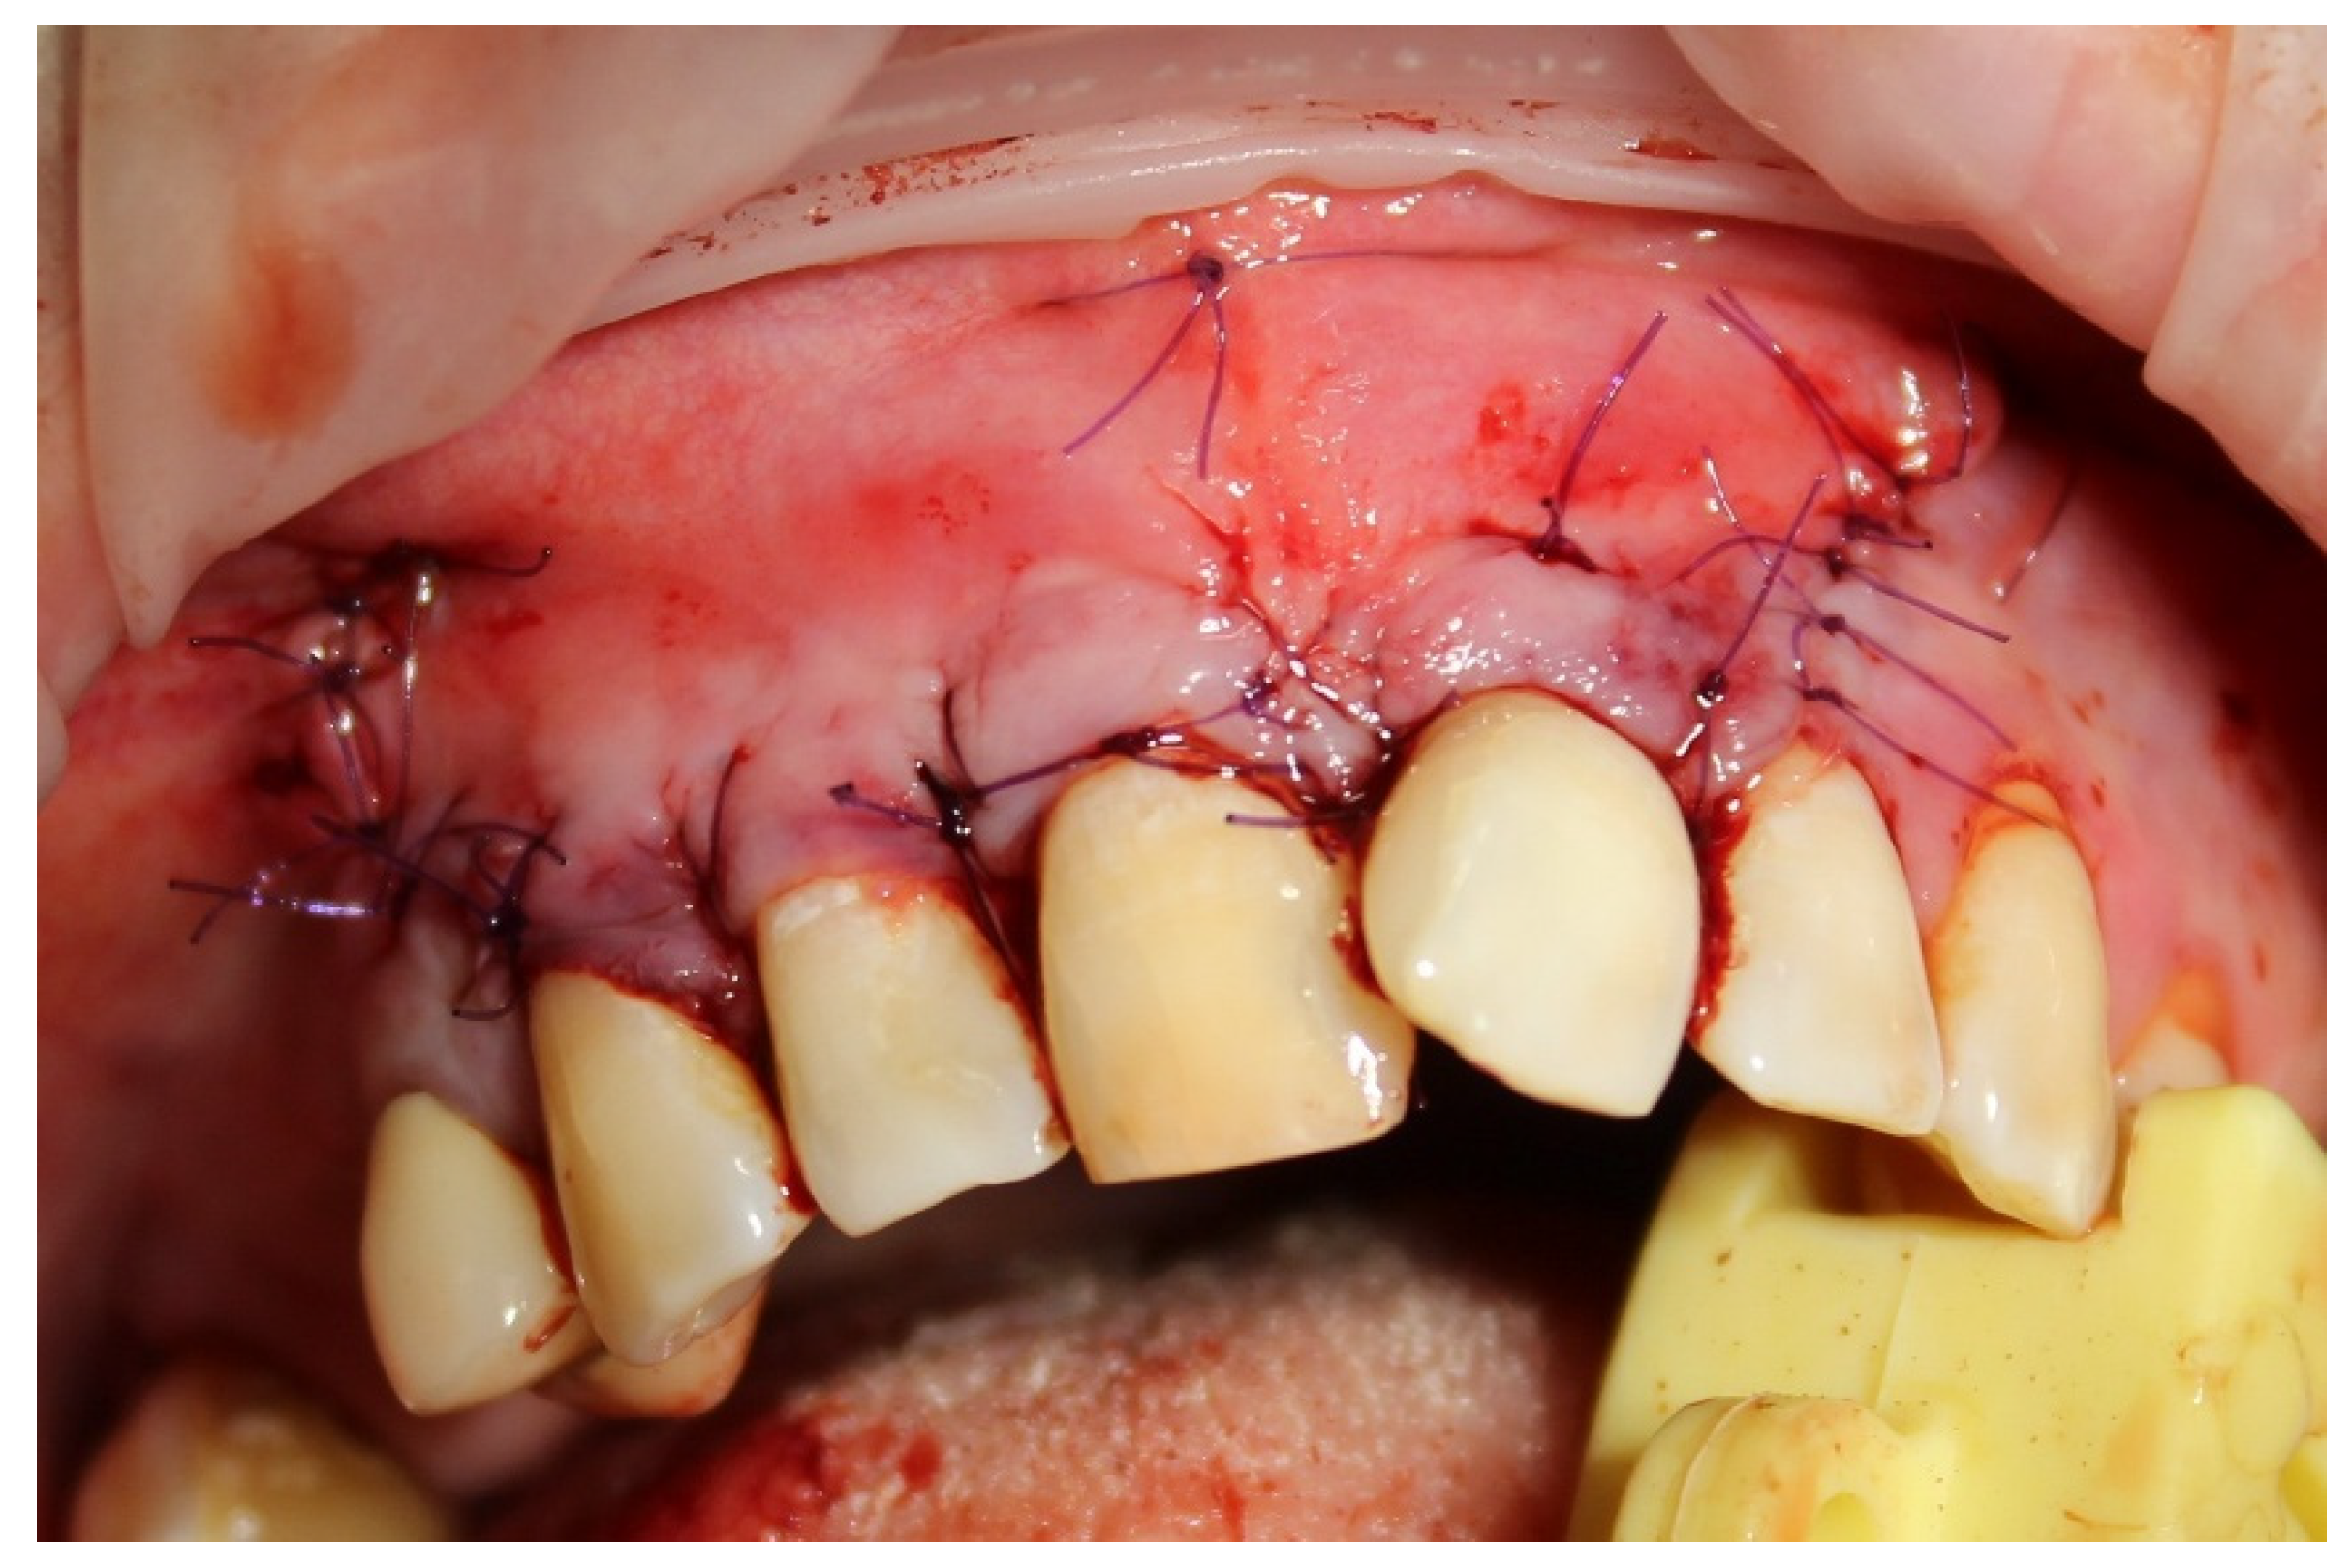

For one month, the patient received complex conservative therapy to relieve acute inflammation. Before surgery, the cyst-related teeth 1.3, 1.2, 1.1 and 2.1 were endodontically treated. Cyst enucleation was performed with preliminary sedation under local anesthesia. Following the enucleation, histopathological analysis confirmed the presence of a radicular cyst. The apices of the teeth roots 1.3, 1.2, 1.1 and 2.1 protruding into the periradicular lesion were resected, the residual bone cavity was filled with PRF clot (Figure 2), and the bone wound was completely covered with a mucoperiosteal flap (Figure 3).

Figure 3. Bone wound is completely covered with a mucoperiosteal flap.